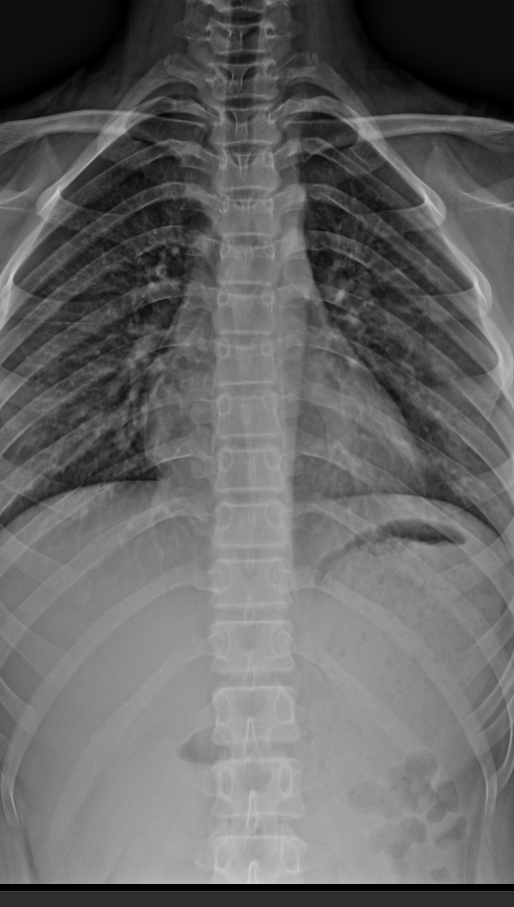

T-spine AP

- CR 중심점은 견갑골하각에 중심을 맞춘다.

- 혹은 T-7에 맞추면 되는데, 환자에게 명치를 짚으라 한 후 위로 손가락 한두마디 정도 올라가면 된다.

- 거리 100cm

- 조건 80kV/10mAs (고전압 사용시 대비 감소)

- 그리드(grid) 사용

- 호기 후 촬영

- 누워서(supine) 촬영시 무릎을 세워 허리 뜸을 방지한다.

중심점(CR), 거리(distance)

- 검상돌기(xiphoid process)에 수직입사

- 100~150cm

노출조건

- 80KvP / 10mAs

- Grid(+)

- 호기시 멈춤 후 촬영

T-spine Lat

- 선 자세(Erect)

- 심장 음영과 척추 겹침을 최소화 하기 위해 몸 왼쪽을 카세트에 붙인다.

- 척추측만(scoliosis) 이 있을 경우, 볼록한 면을 디텍터쪽으로 붙인다.

- 팔을 들어올린다.

- 견갑골 하각(inferior angle of scapula) 에 중심선을 맞춘다.

- 옆으로 누운 자세(Decubitus)

- 심음영과 척추의 겹침을 최소화하기 위해 왼쪽으로 돌려 눕는다.

- 척추측만의 경우 볼록한 면을 디텍터쪽으로 붙인다.

- 베게 혹은 블럭을 머리, 허리, 다리사이에 끼워넣어 척추 정렬을 보상한다.

- 견갑골하각 높이에서 손가락 4개 너비 지점에 수직입사

- 80KvP / 8mAs

- 숨을 참는다.

- 호흡시 장노출(2~3sec)로

이미지